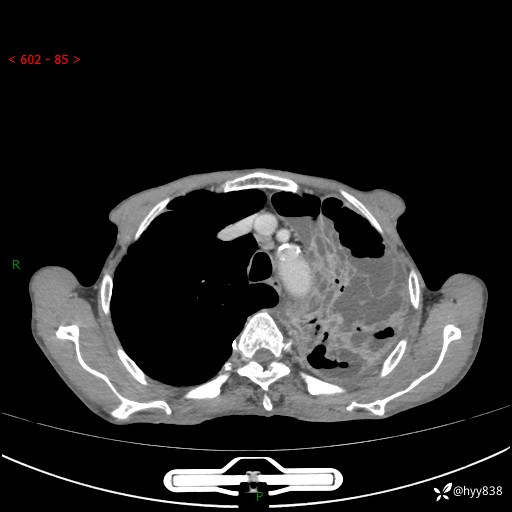

胸部CT平扫+增强